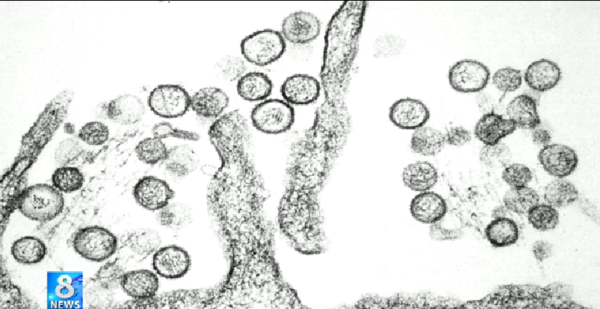

살인 진드기가 국내에서 발견됐다는 소식에 관심이 증폭되고 있다.집 진드기보다 10배 이상 큰 이 살인진드기는 플레보바이러스를 옮기며 치사율이 12~30%에 이르는 것으로 알려졌다.질병관리본부에 따르면 진드기가 옮기는 것으로 알려진 바이러스인 '중증 열성 혈소판 감소 증후군(SFTS)'에 대한 감시와 역학조사 활동을 강화하고 있다.이 진드기는 독을 갖고 있지 않으나 진드기 몸속에 있는 '플레보 바이러스'가 위험하다.이 바이러스가 인체에 침입하면 고열과 함께 구토와 설사 증상이 나타난다.심한 경우 혈액 중의 혈소판이 줄어들면서 장기 손상으로 숨질 수도 있다.이에 따라 보건당국 ""감염 가능성에 대비해 풀밭에서 긴 소매 옷을 입고 오래 누워있지 말 것"을 당부했다.